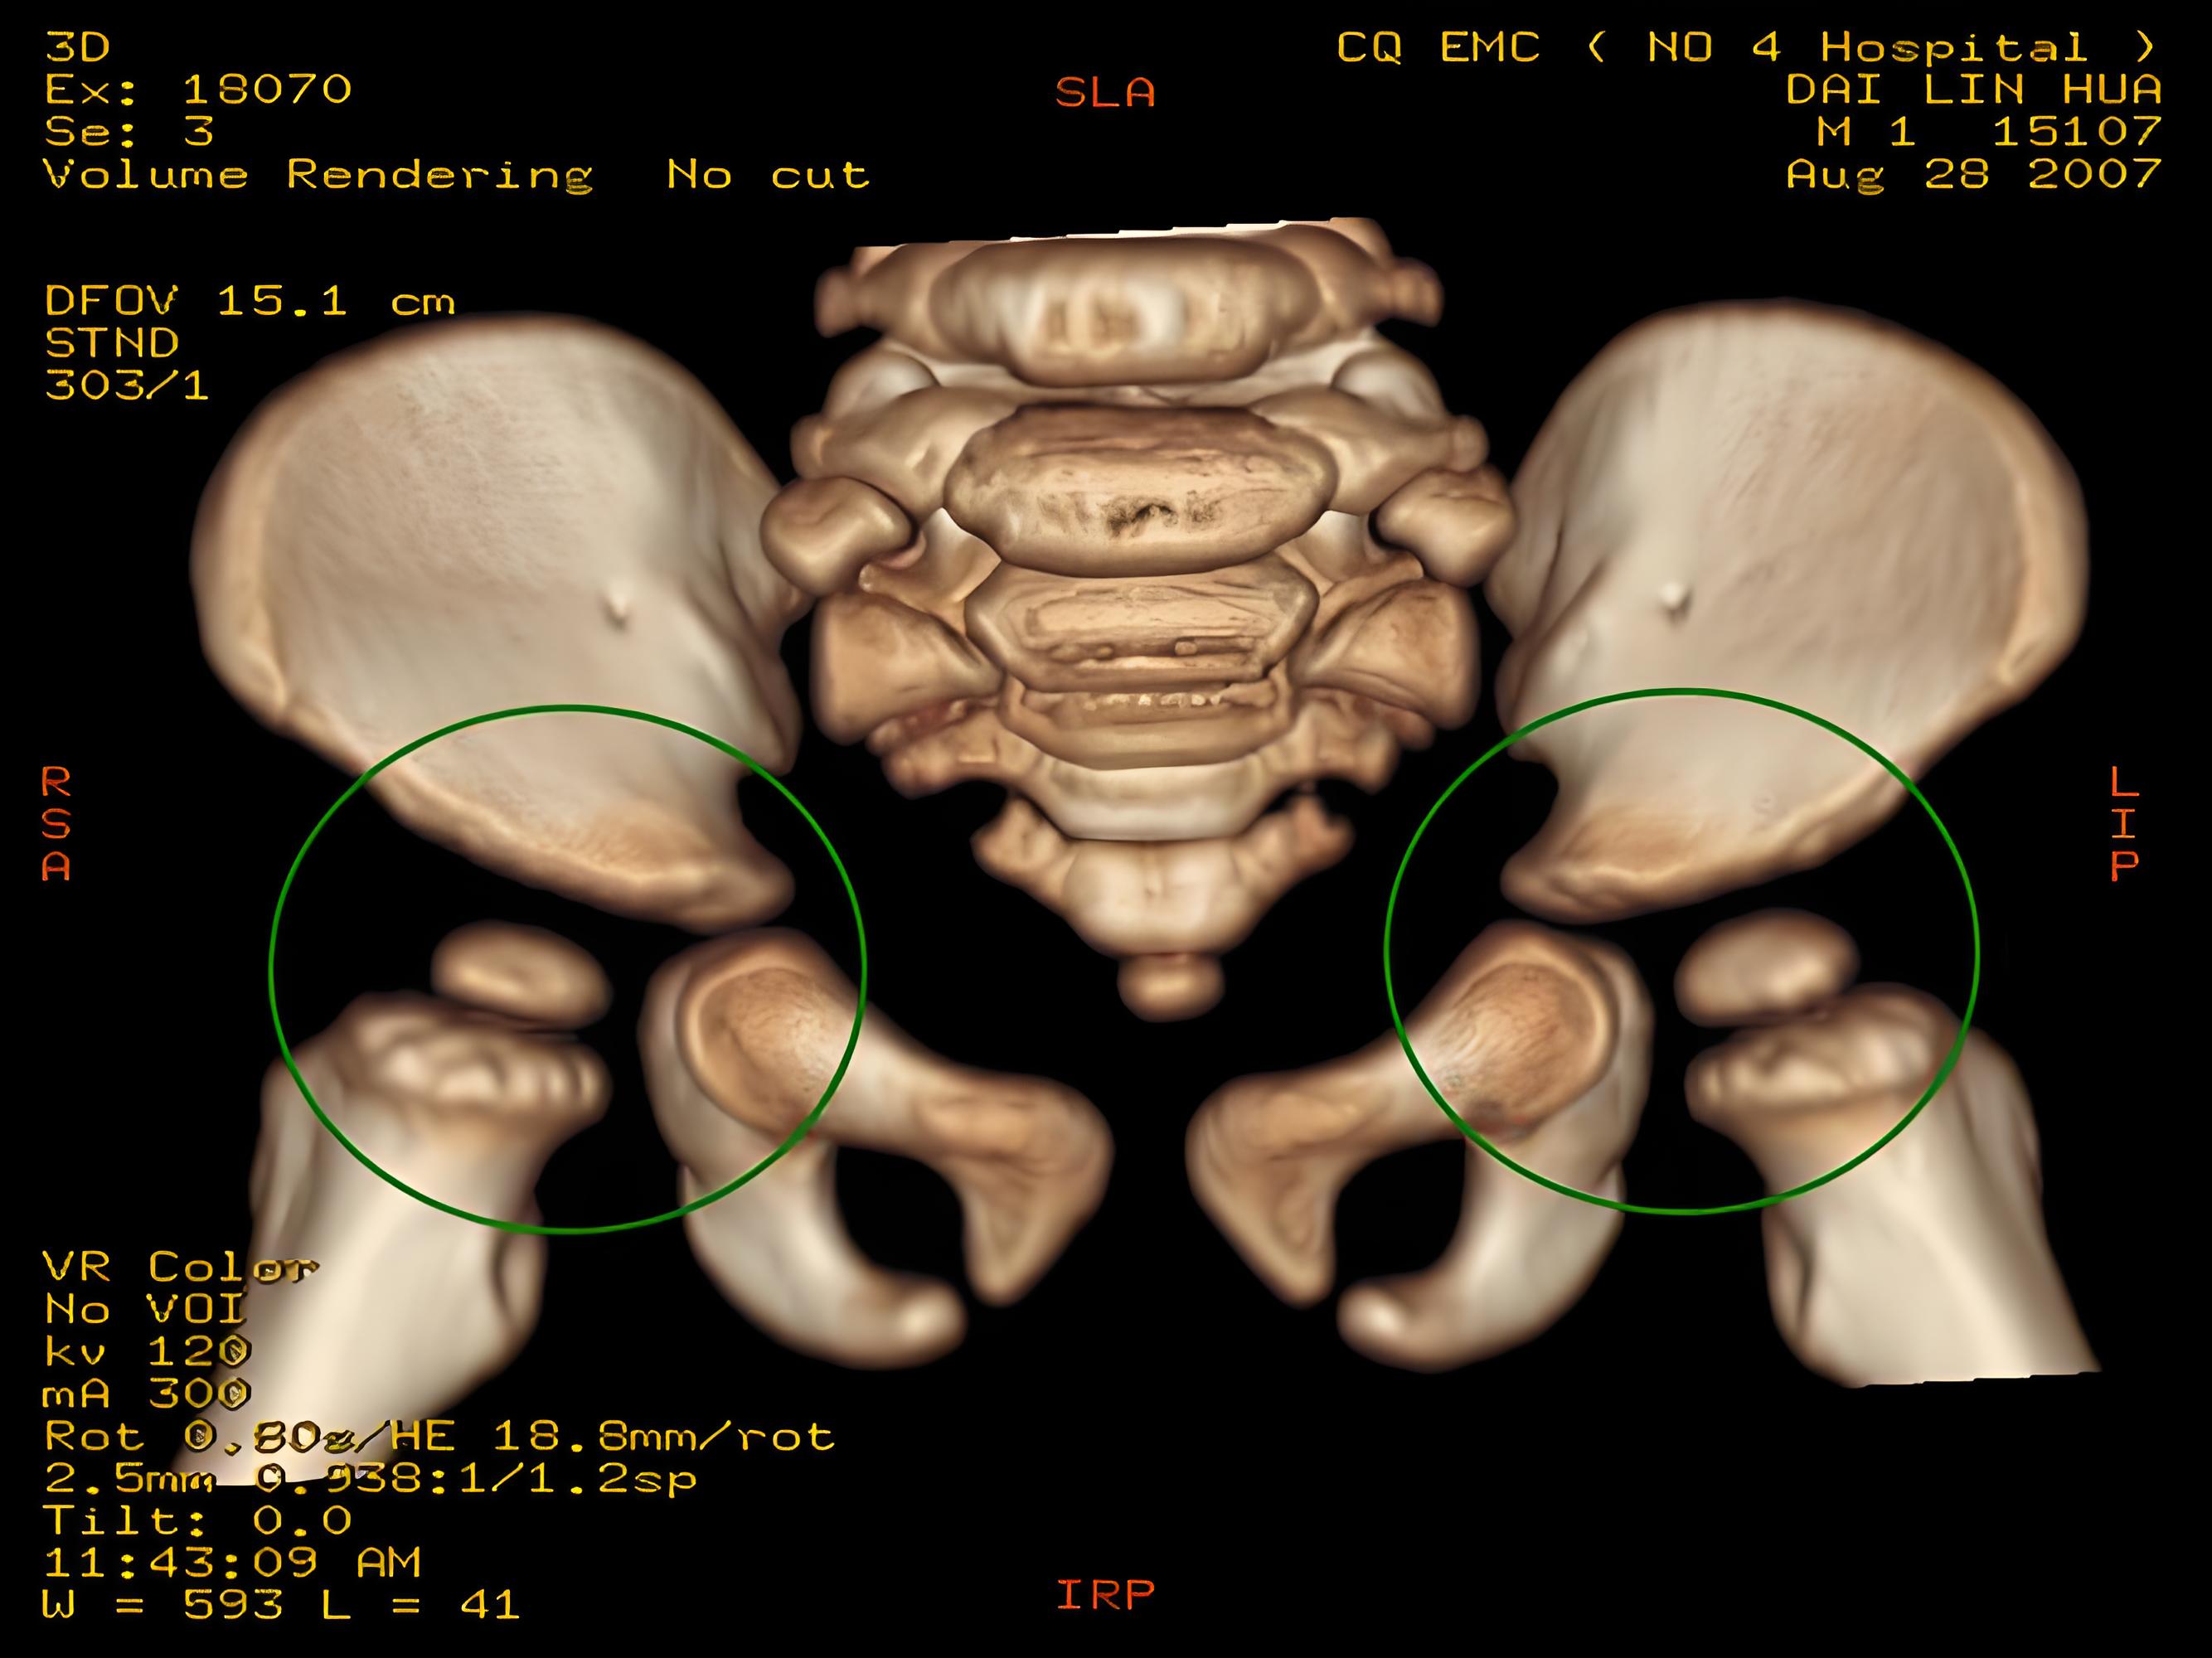

ct入门手把手教你读懂髋关节ct详细标注版

发育性髋关节发育不良是什么疾病?

骨盆正位(髋臼发育不良,股骨头缺血性坏死,髋外翻)